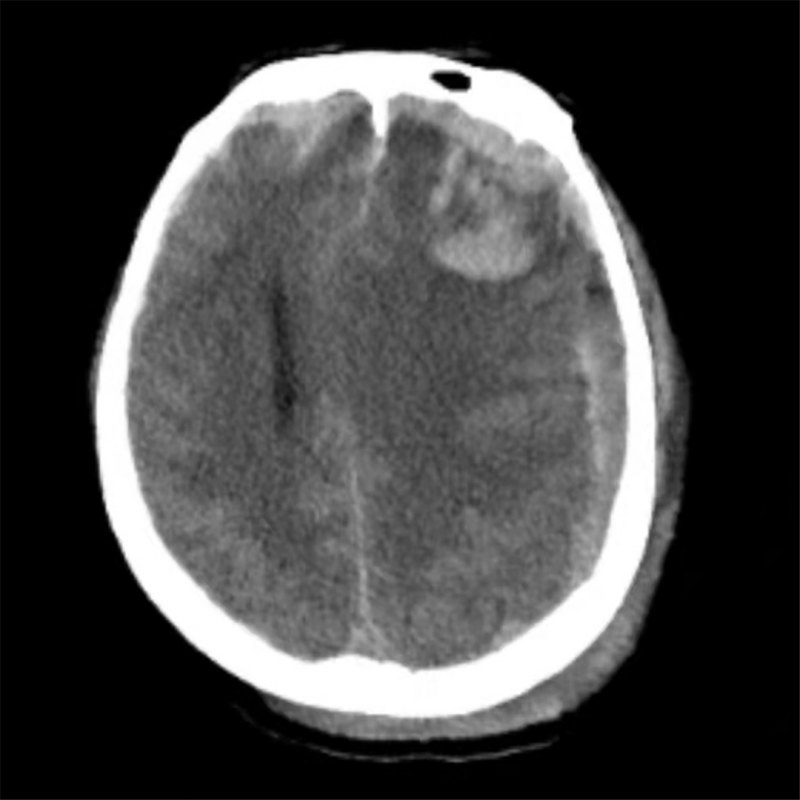

术前颅脑CT可见:颅脑多发挫裂伤、左侧额颞顶部急病硬膜下出血,脑组织受压明显。

王先生入院时颅脑CT提示:颅内多发性大脑挫裂伤、急性创伤性硬膜下出血且合并脑疝(一种颅脑急危重症,可迅速致人死亡)。东院神经外科夏广文副主任医师查看病人后,对其病情进行评估:病人意识处于深昏迷状态,颅内出血量大,中线结构移位明显。遂立即完善术前准备,急诊手术治疗。术中见颅内弥漫性出血,多发挫裂伤,夏广文仔细为其清除血肿及挫伤灶。术后,王先生住进东院急诊重症监护病房,在潘继明副主任医师医疗团队的治疗下,最终转危为安。